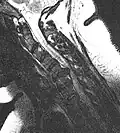

Cervical disc herniation

Cervical disc herniations occur in the neck, most often between the fifth and sixth (C5–6) and the sixth and seventh (C6–7) cervical vertebral bodies. There is an increased susceptibility amongst older (60+) patients to herniations higher in the neck, especially at C3–4.[23] Symptoms of cervical herniations may be felt in the back of the skull, the neck, shoulder girdle, scapula, arm, and hand.[24] The nerves of the cervical plexus and brachial plexus can be affected.[25]

- Magnetic resonance imaging is the gold standard study for confirming a suspected LDH. With a diagnostic accuracy of 97%, it is the most sensitive study to visualize a herniated disc due to its significant ability in soft tissue visualization. MRI also has higher inter-observer reliability than other imaging modalities. It suggests disc herniation when it shows an increased T2-weighted signal at the posterior 10% of the disc. Degenerative disc diseases have shown a correlation with Modic type 1 changes. When evaluating for postoperative lumbar radiculopathies, the recommendation is that the MRI is performed with contrast unless otherwise contraindicated. MRI is more effective than CT in distinguishing inflammatory, malignant, or inflammatory etiologies of LDH. It is indicated relatively early in the course of evaluation (<8 weeks) when the patient presents with relative indications like significant pain, neurological motor deficits, and cauda equina syndrome. Diffusion tensor imaging is a type of MRI sequence used for detecting microstructural changes in the nerve root. It may be beneficial in understanding the changes that occur after herniated lumbar disc compresses a nerve root, and might help in differentiating the patients that need surgical intervention. In patients with a high suspicion of radiculopathy due to lumbar disc herniation, yet the MRI is equivocal or negative, nerve conduction studies are indicated.[44] T2-weighted images allow for clear visualization of protruded disc material in the spinal canal.

-

MRI scan of cervical disc herniation between C5 and C6 vertebrae -

MRI scan of cervical disc herniation between C6 and C7 vertebrae -